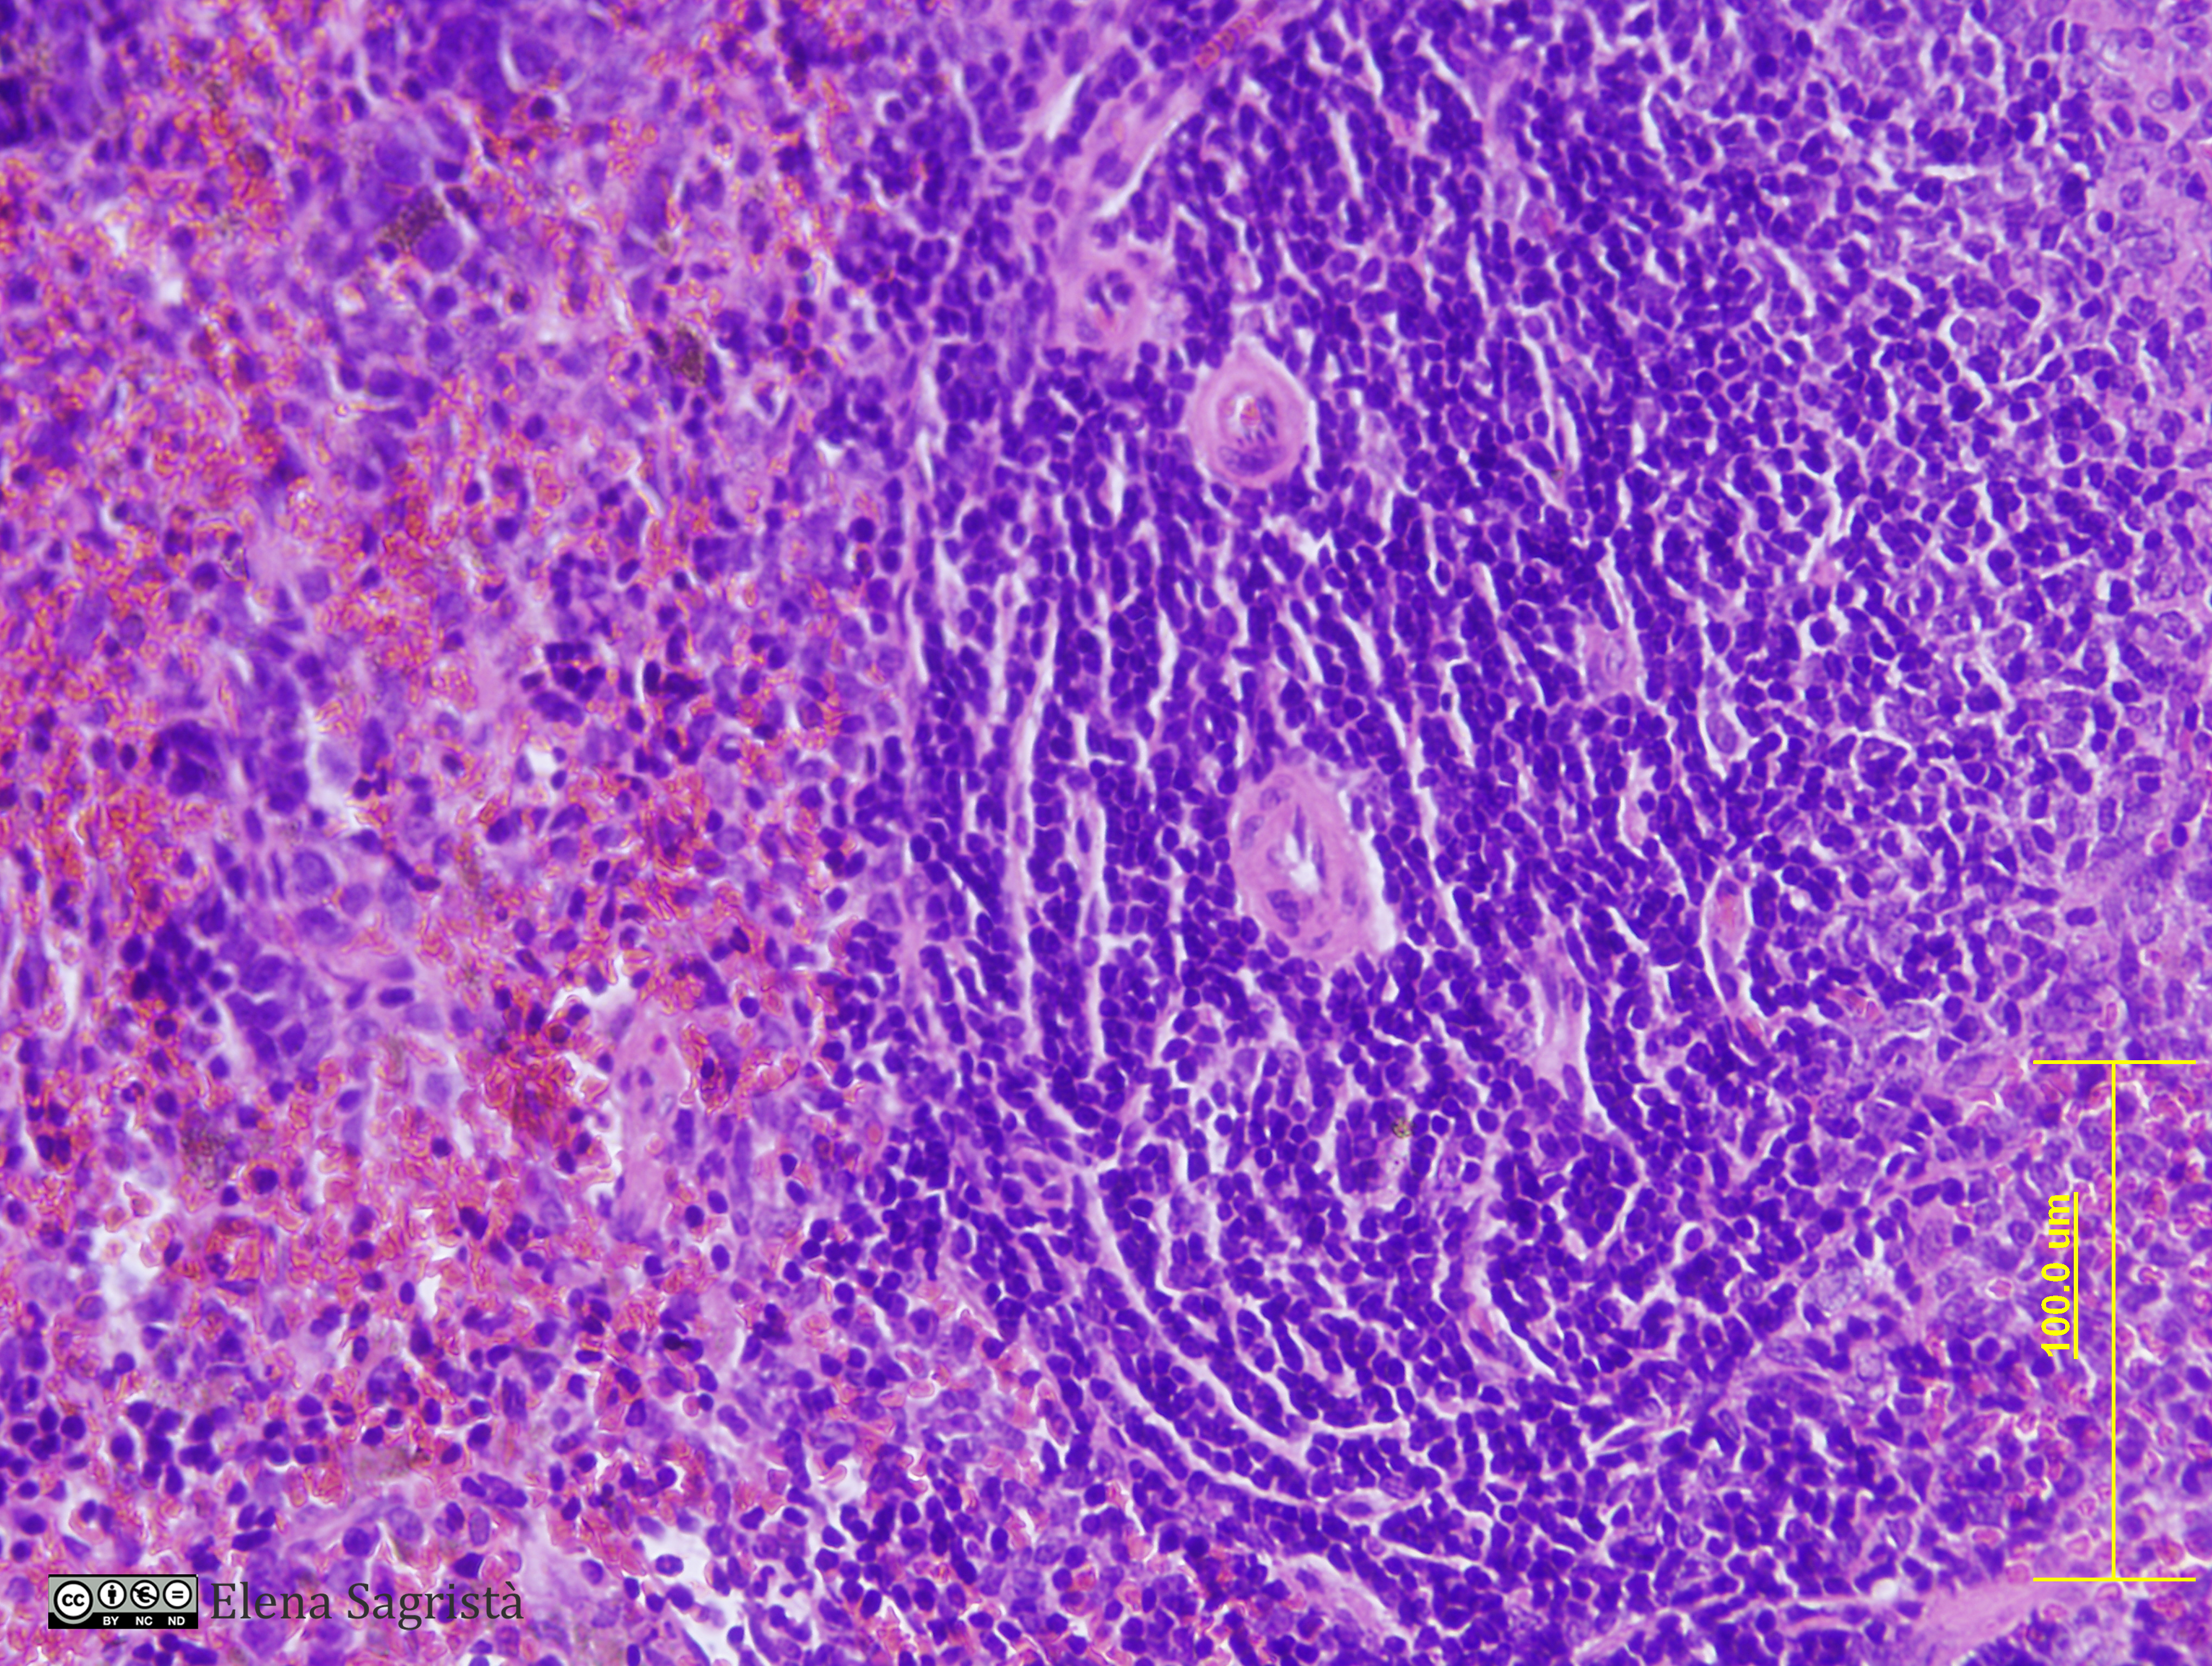

Histologia imatges: 23 Sang, Melsa, Tim i Vas limfàtic

Imatges de preparacions histològiques de Sang, Melsa, Tim i Vas limfàtic. Microscòpia òptica.

SAGRISTÀ I MATEO, Elena, Universitat de Barcelona. Departament de Biologia Cel·lular. Histologia imatges: 23 Sang, Melsa, Tim i Vas limfàtic. [consulta: 6 de maig de 2026]. [Disponible a: https://hdl.handle.net/2445/61480]